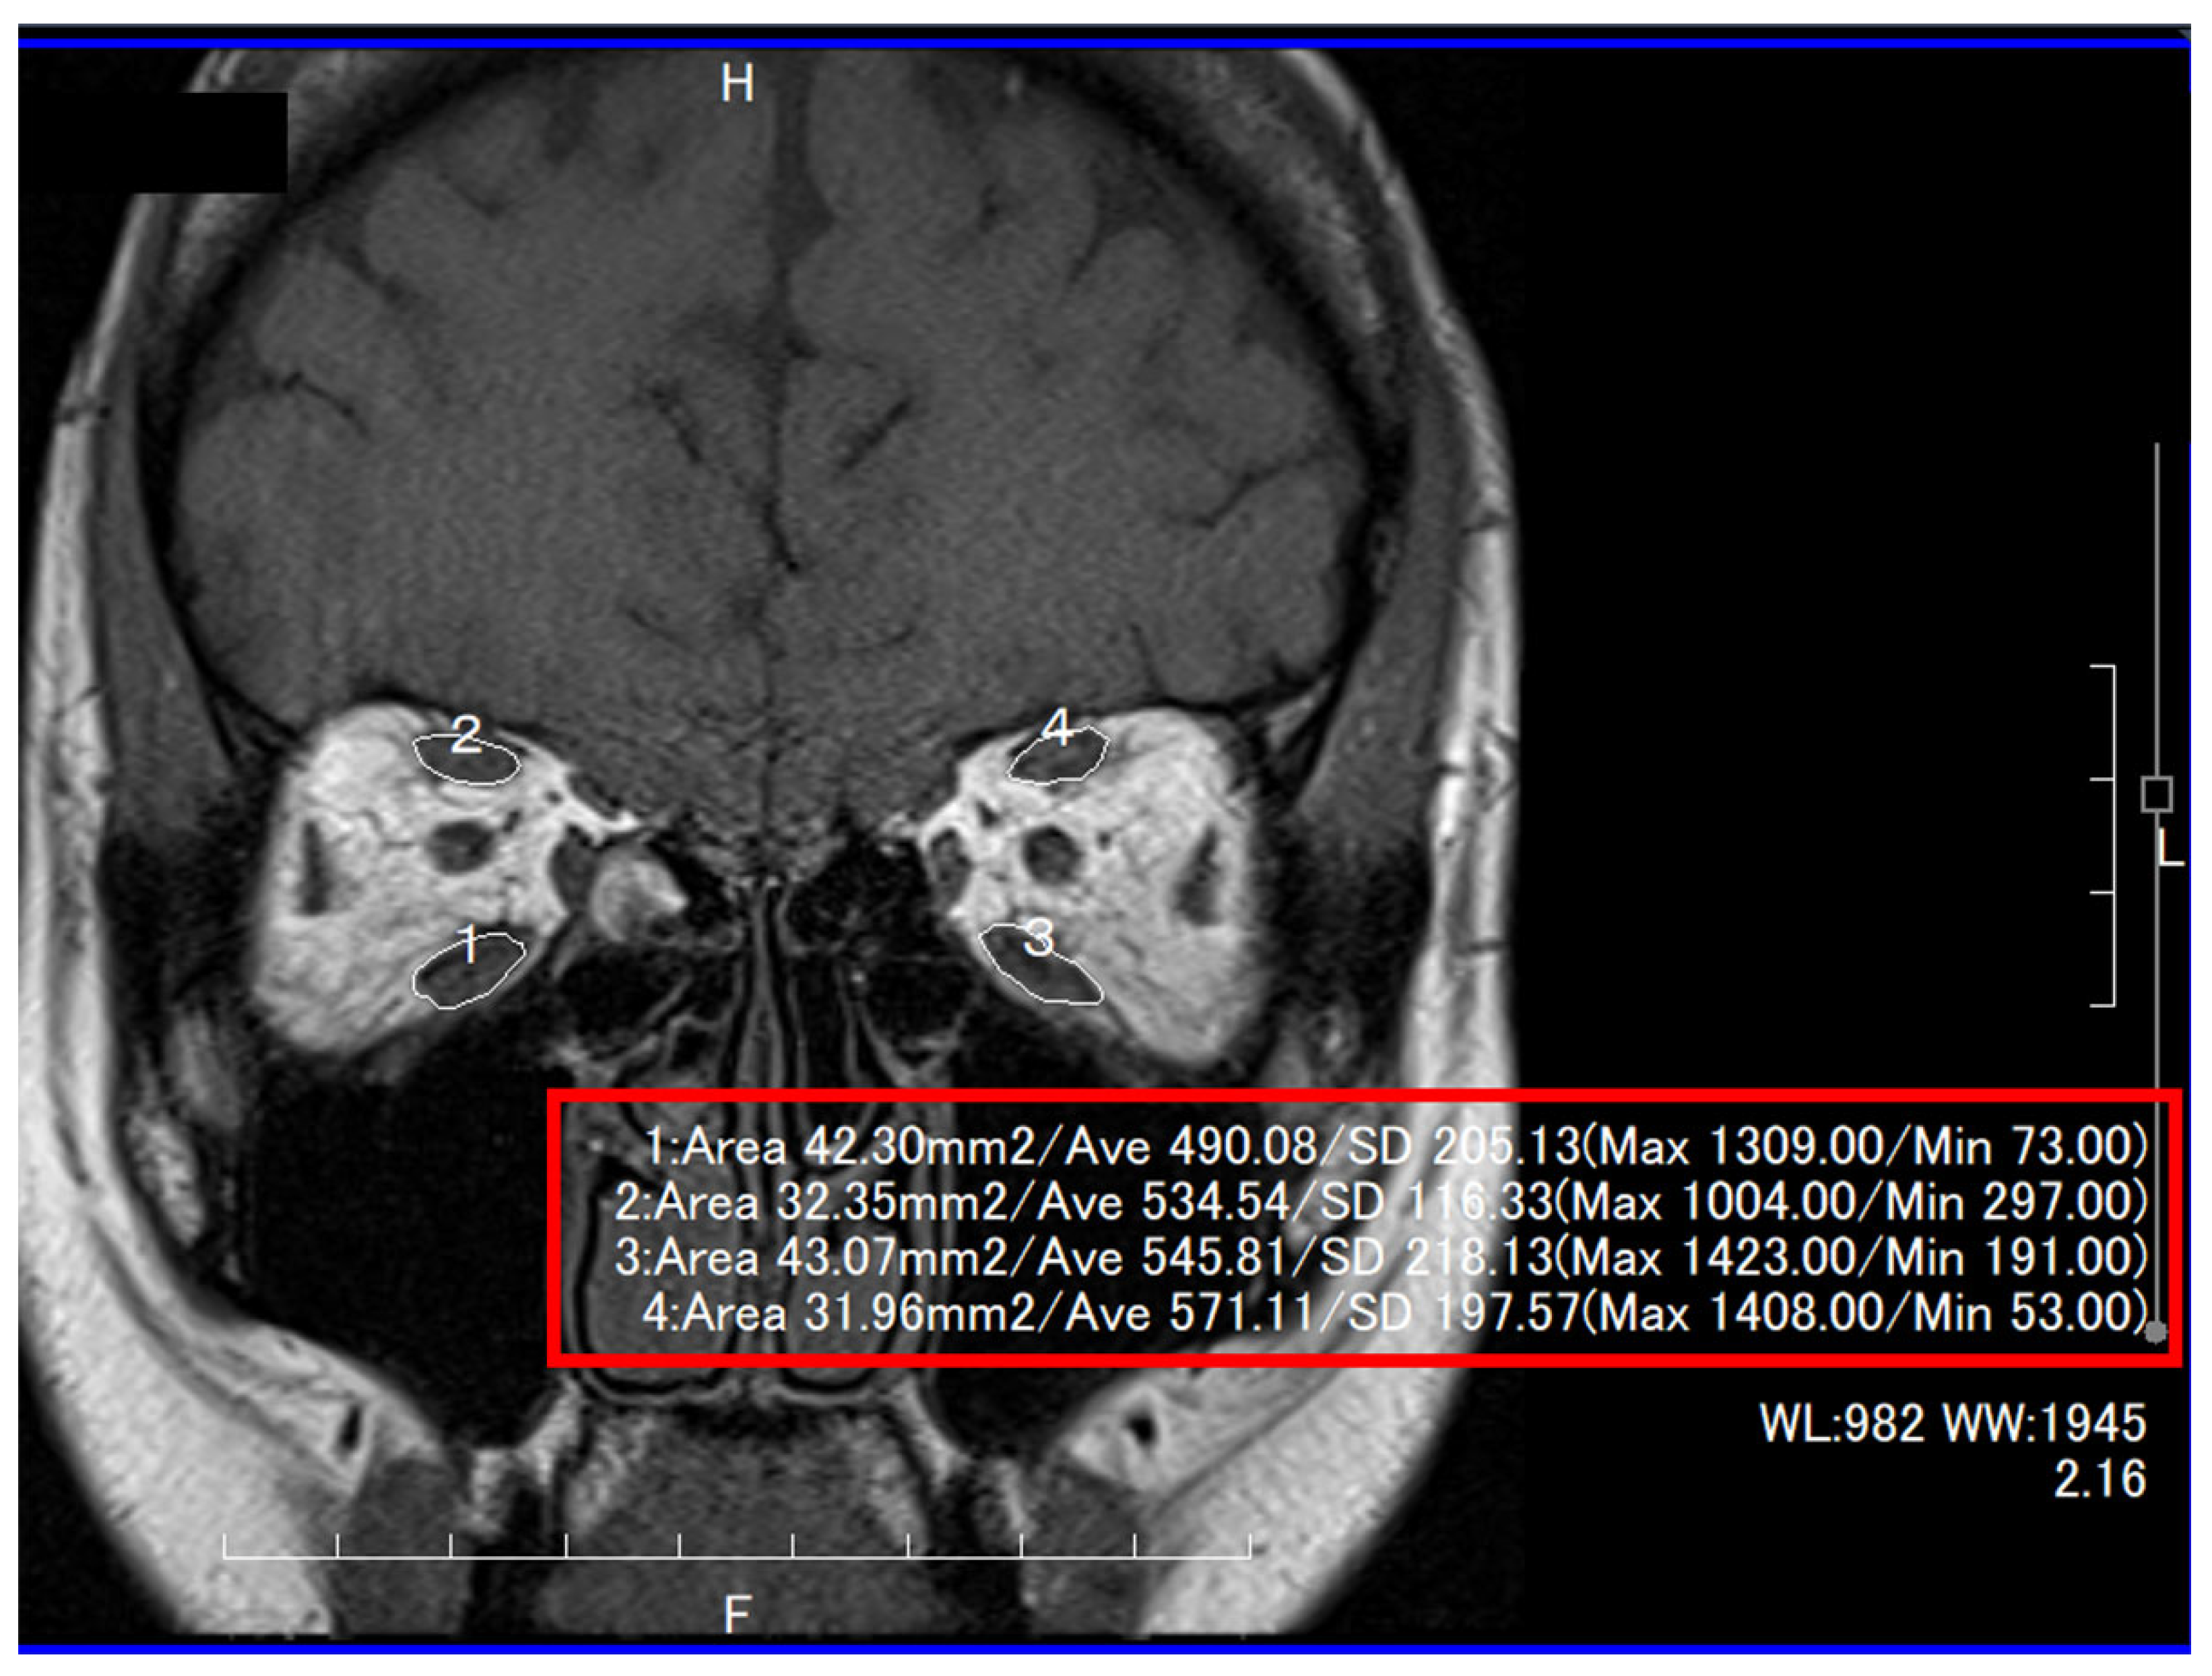

MRI was performed using a 1.5-Tesla scanner (Magnetom Abant™; Siemens Healthcare, Erlangen, Germany), with the patients in the supine position. Coronal T1- and T2-weighted gradient-echo sequences were acquired (T1—repetition time: 500 ms, echo time: 10 ms, field of view: 140 × 140 mm, matrix: 256 × 220, section thickness: 3 mm with a 0.6 mm gap between slices; T2—repetition time: 4000 ms, echo time: 100 ms; all other parameters were the same as in T1). Patients were asked to look at a light source to ensure that their eyes were fixed in the primary position. The cross-sectional areas of the IR, SR, MR, and SO muscles on a coronal T1-weighted MRI image and those of the lateral rectus muscle on an axial T1-weighted MRI image at the largest point were measured by one of the authors (Y.T.), using the measuring tool available in the MRI viewer (ShadeQuest/ViewR™; Yokogawa Medical Solutions Corporation, Tokyo, Japan) (Figure 2) [24]. This study did not measure the cross-sectional area of the inferior oblique muscle because sagittal images could not be obtained from some of the patients [25].

Figure 2.

Measurements of the cross-sectional areas of inferior (#1 and #3) and superior (#2 and #4) recti muscles.